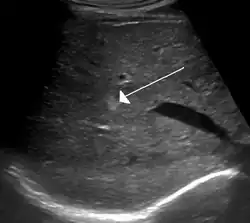

Hemangioma of the liver as seen on ultrasound

A cavernous liver hemangioma or hepatic hemangioma is a benign tumour of the liver composed of hepatic endothelial cells. It is the most common liver tumour, and is usually asymptomatic and diagnosed incidentally on radiological imaging. Liver hemangiomas are thought to be congenital in origin.[10] Several subtypes exist, including the giant hepatic hemangioma, which can cause significant complications.